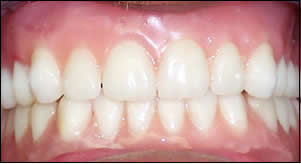

Fig 9: A frontal view of centric occlusion .The upper denture in place. The lower overdenture clipped into place.